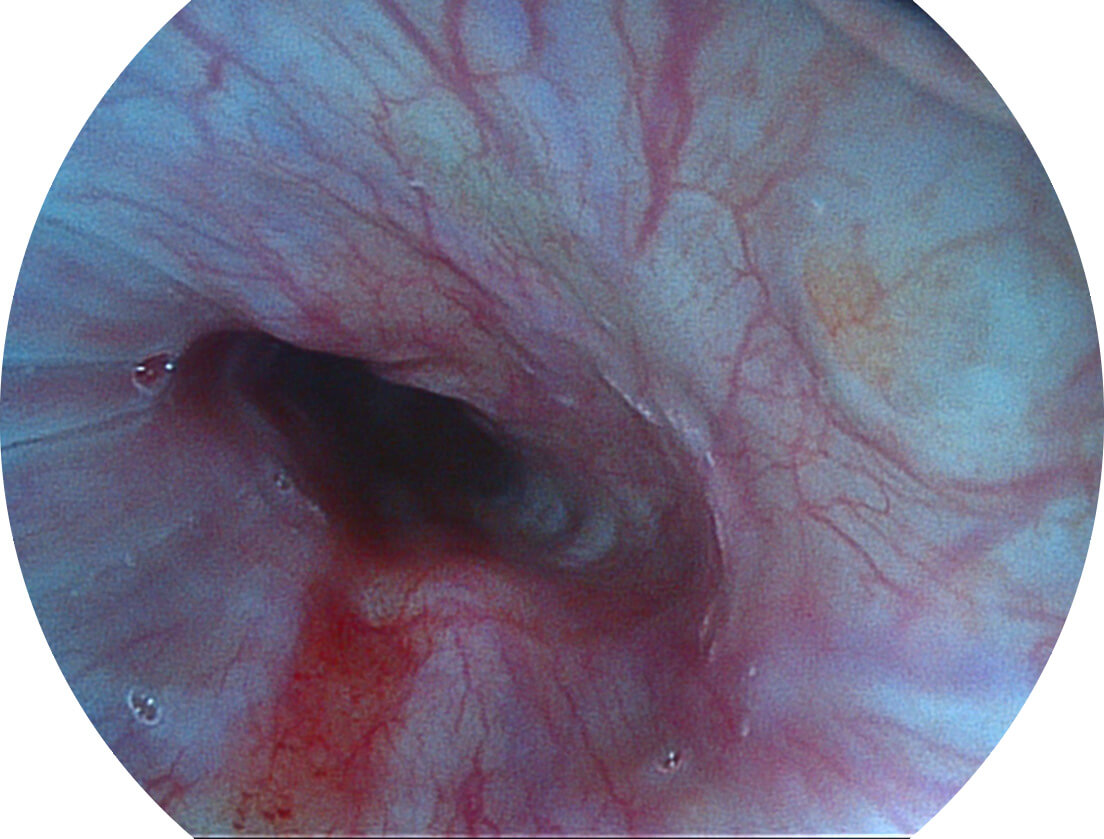

白光图像

SFI图像

强调浅层黏膜结构的同时,保证照明亮度和提升浅层微血管与中层血管颜色对比度,病变边界更清晰。